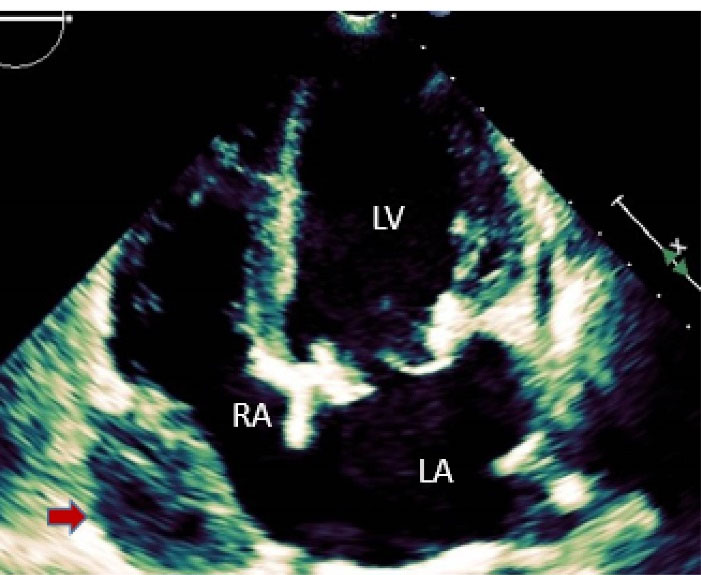

A 57-year-old lady with history of rheumatic mitral valve disease underwent mitral valve replacement by Saint Jude Medical Epic bioprosthesis in our high-volume mitral surgery center. Preoperative coronary angiography was non-significant except for a moderate stenosis of mid left anterior descending artery (LAD) (). The patient underwent coronary artery bypass grafting (CABG) using left internal mammary artery (LIMA) to LAD concomitantly with mitral valve surgery. The surgery was smooth with no postoperative complications. On serial postoperative electrocardiogram (EKG), there was no ST segment elevation or new significant ischemic changes compared to preoperative EKG. Routine postoperative echocardiogram showed good function of the mitral prosthesis and good global function of the left ventricle. Four weeks later, the patient started to have dyspnea, orthopnea and other symptoms of heart failure. EKG showed non-significant ST-T changes (). Echocardiography showed severely impaired left ventricle (LV) systolic function. Moreover, there was a localized hematoma adjacent to the right atrium without hemodynamic impact (). In light of these findings along with elevated troponin level, we decided to repeat coronary angiography. The later showed complete occlusion of the proximal LCX () and stenosis of the LIMA -LAD anastomosis. A PCI strategy was successful for LIMA-LAD stenosis () but difficult for LCX lesion; after crossing the lesion using work-horse wire, and use of different size non-compliant and compliant balloons, there was continuous recoil after balloon deflation (). The trial of angioplasty and stenting was failed with no recuperation of distal flow. Therefore, we suspected surgical complication with mechanical compression of the circumflex coronary artery most probably by encircling suture loop, in addition to stenosis of the LIMA-LAD. Furthermore, the retro atrial hematoma might be caused by epicardial coronary artery injury. The procedure was then stopped and the patient was kept on medical treatment. On follow up visits, there was complete resolution of the atrial hematoma, and a significant improvement of LV function on standard heart failure treatment.

Figure 2. Transthoracic echocardiography, apical 4 chambers view: A hematoma around the right atrium is seen (red arrow).